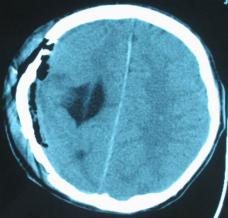

头颅正侧位片:可见右顶部颅骨缺损区,局部软组织隆起,类长圆形,缺损边缘不规则、骨质密度增高合并骨质破坏密度减低,隆起如火山口状(图1)。

图1:(1)正位相见右顶部骨质缺损,局部软组织隆起,边缘不规则,骨质密度增高合并骨质破坏密度减低,隆起如火山口状;(2)侧位相见颅骨缺损区,类似长圆形,缺损边缘不规则